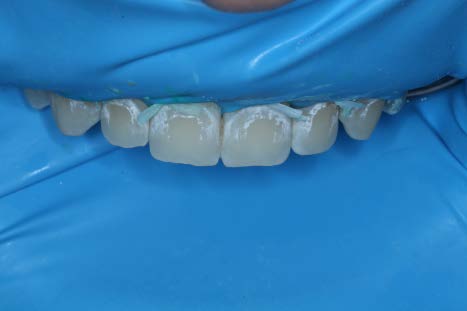

After the third round of etching, Icon Dry was applied and the lesions were almost completely camouflaged. Note that in the picture the lesions appear worse than original when dry, however, when the Icon Dry alcohol or resin Infiltrant are applied, the color improves drastically.

After allowing the Icon Dry to sit for 30 seconds and thoroughly drying the teeth, the resin Icon Infiltrant was applied for 3 minutes. The overhead light was removed and the resin was refreshed every minute. The excess resin was then blown away with an air-water tip and the teeth were flossed. Each tooth was then light cured for 40 seconds. A second round of infiltration was then applied, cured and a scaler was used to remove excess resin.